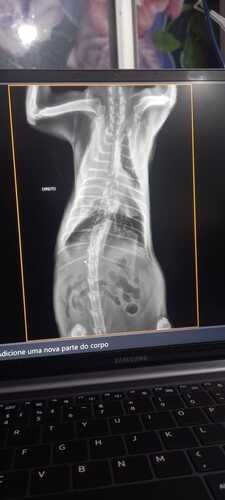

Fomos na oncologista que infelizmente confirmou que todos os problemas de saúde da nossa heroína são devidos a um linfoma que está empurrando o seu coração, apertando o seu peitinho.. Fizemos o teste e ela deu como FELV positivo, infelizmente. Isso deixa o caso ainda mais complicado.

Só que os custos vão ficando muito caros, internação, exames, tirar e examinar o líquido, raio x, exame de sangue, ultrassom e até um exame cardiológico pois suspeitamos que seja o coração.